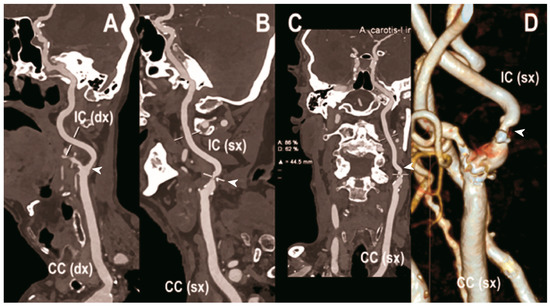

5.2. Neuroimaging

Carotid artery atherosclerosis is considered a major risk factor for ischemic stroke and transient ischemic attacks (TIA) [100]. The accurate characterization of lumen narrowing together with plaque morphology are the key for an improved risk stratification of patients and the design of tailored medical therapy and surgical intervention [101]. CTA of the neck and brain vessels is routinely done in patients with suspected cerebrovascular stroke, but the calcified plaques leading to blooming and beam-hardening artifacts negatively impact the image quality [102]. In this context, all the added benefits of PCCT translate into improved imaging (Figure 3, Figure 4 and Figure 5).

Figure 3.

Carotid CT angiography using photon-counting computed tomography. The figure shows advanced reconstructions of a carotid artery tree derived from a photon-counting CT (Scanner: NAEOTOM Alpha, Siemens) acquisition (A–D). In (A), a longitudinal multiplanar reconstruction shows the right common and internal carotid artery with no significant luminal stenosis and a predominantly calcified atherosclerotic plaque at the carotid bifurcation (arrowhead). In (B), a longitudinal multiplanar reconstruction shows the left common and internal carotid artery with a significant luminal stenosis in the post-bulbar region of the internal carotid artery (arrowhead). In (C) the quantitative assessment of the stenosis (arrowhead) and in (D) the 3-dimensional volume rendering of the lesion (arrowhead).

Figure 4.

Carotid CT angiography using photon-counting computed tomography. The figure shows advanced reconstructions of a carotid artery tree derived from a photon-counting CT (Scanner: NAEOTOM Alpha, Siemens) acquisition (A–D). In (A,B), a longitudinal multiplanar reconstruction shows the right common and internal carotid artery with no significant luminal stenosis and a mild predominantly calcified atherosclerotic plaque at the internal carotid origin (arrowhead). In (C,D), a longitudinal multiplanar reconstruction shows the left common and internal carotid artery with a minimal arterial wall irregularity at the internal carotid origin (arrowhead). What is a bit unusual is to be able to see the thickness of the arterial wall at this level in a case with very mild atherosclerotic disease.

The capability of PCCT technology to improve carotid and intracranial angiography has been demonstrated in vivo in a pilot study involving 16 asymptomatic subjects [49]. Compared to conventional CT, PCCT offered less image noise (9%) and beam-hardening artifacts in internal carotids close to the surrounding bone. Accordingly, the two radiologists blinded to the detector subsystem attributed to the images obtained with PCCT significantly higher quality scores for all vascular segments. Finally, the above-mentioned study showed the feasibility of spectral material decomposition of PCCT in the neck and brain for vascular imaging, although a direct comparison of the spectral performance between PCD and comparable dual energy EID CT scanners was not performed.